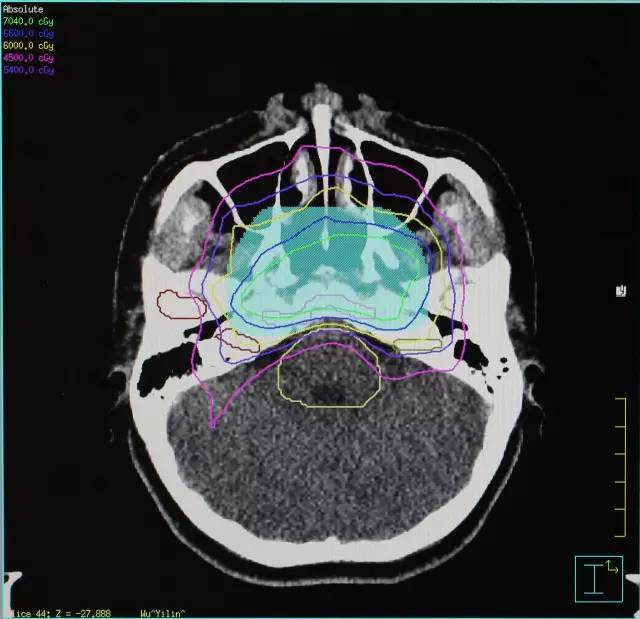

在排除放疗禁忌症之后,开始针对鼻咽癌ct定位后,进行放射治疗,剂量2.

图片尺寸499x280